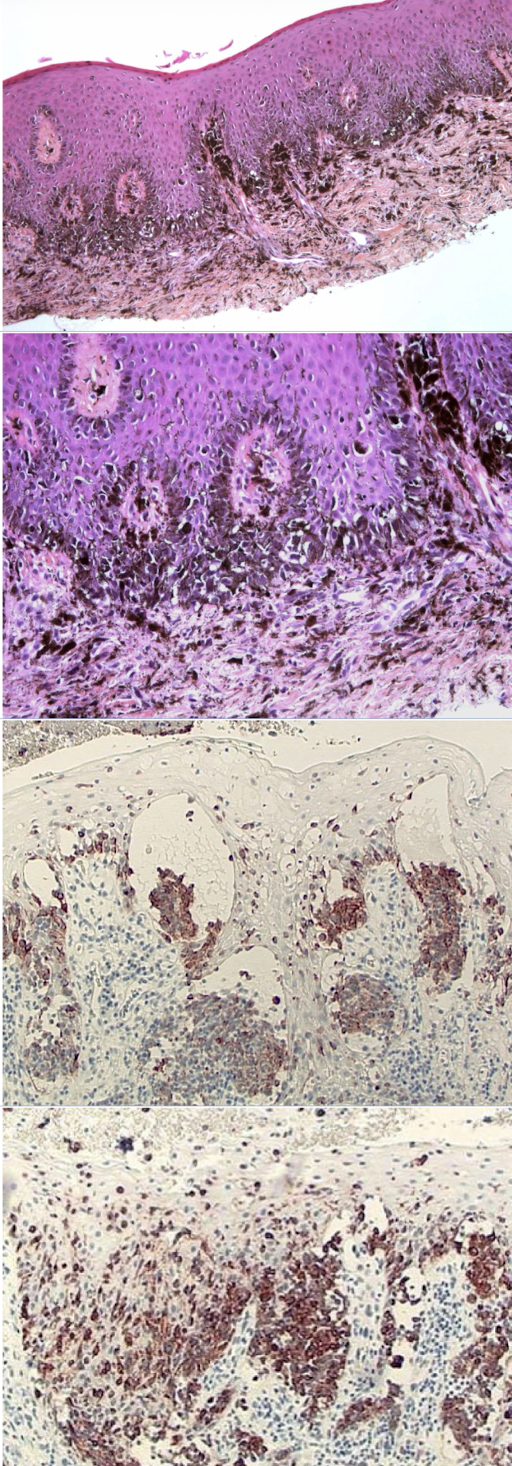

which melanocytic nevus histopathological features?

Unencapsulated proliferation of nevus cells, organized in theques

Lack dendritic processes of melanocytes

Migrate from junctional to compound to intradermal

acquired melanocytic nevus

intramucosal nevus, (unique nevus cells)

nest of melanocytes, unique

Type B to Type C morphology is a key characteristic of benign nevi and a sign of normal cell maturation, which helps pathologists distinguish them from melanoma, where this organized maturation process is typically lost

blue nevus, 1:subtle 2: not subtle

common blue nevus

compound nevus

combined nevus